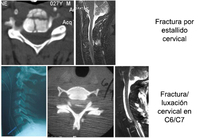

Tipos de fracturas frecuentes con traumatismo grave de la columna cervical. Fila de arriba: fractura por estallido cervical en el nivel C5. Izquierda: imagen de TC axial que muestra una fractura del cuerpo vertebral C5; derecha: IRM ponderada en T2 con plano medio sagital que muestra retropulsión del cuerpo de C5 con compresión de la médula espinal, cambios de señal ponderados en T2 en la médula espinal, y cambios de señal ponderados en T2 en el complejo ligamentario posterior, que indican ruptura de estos ligamentos. Fila de abajo: fractura-luxación en el nivel C6-C7. De izquierda a derecha: radiografía lateral, TC axial en el nivel de carilla articular C6/C7 e IRM con plano medio sagital ponderada en T2 que muestra compresión de la médula espinal y cambio de señal ponderado en T2 en la médula espinal